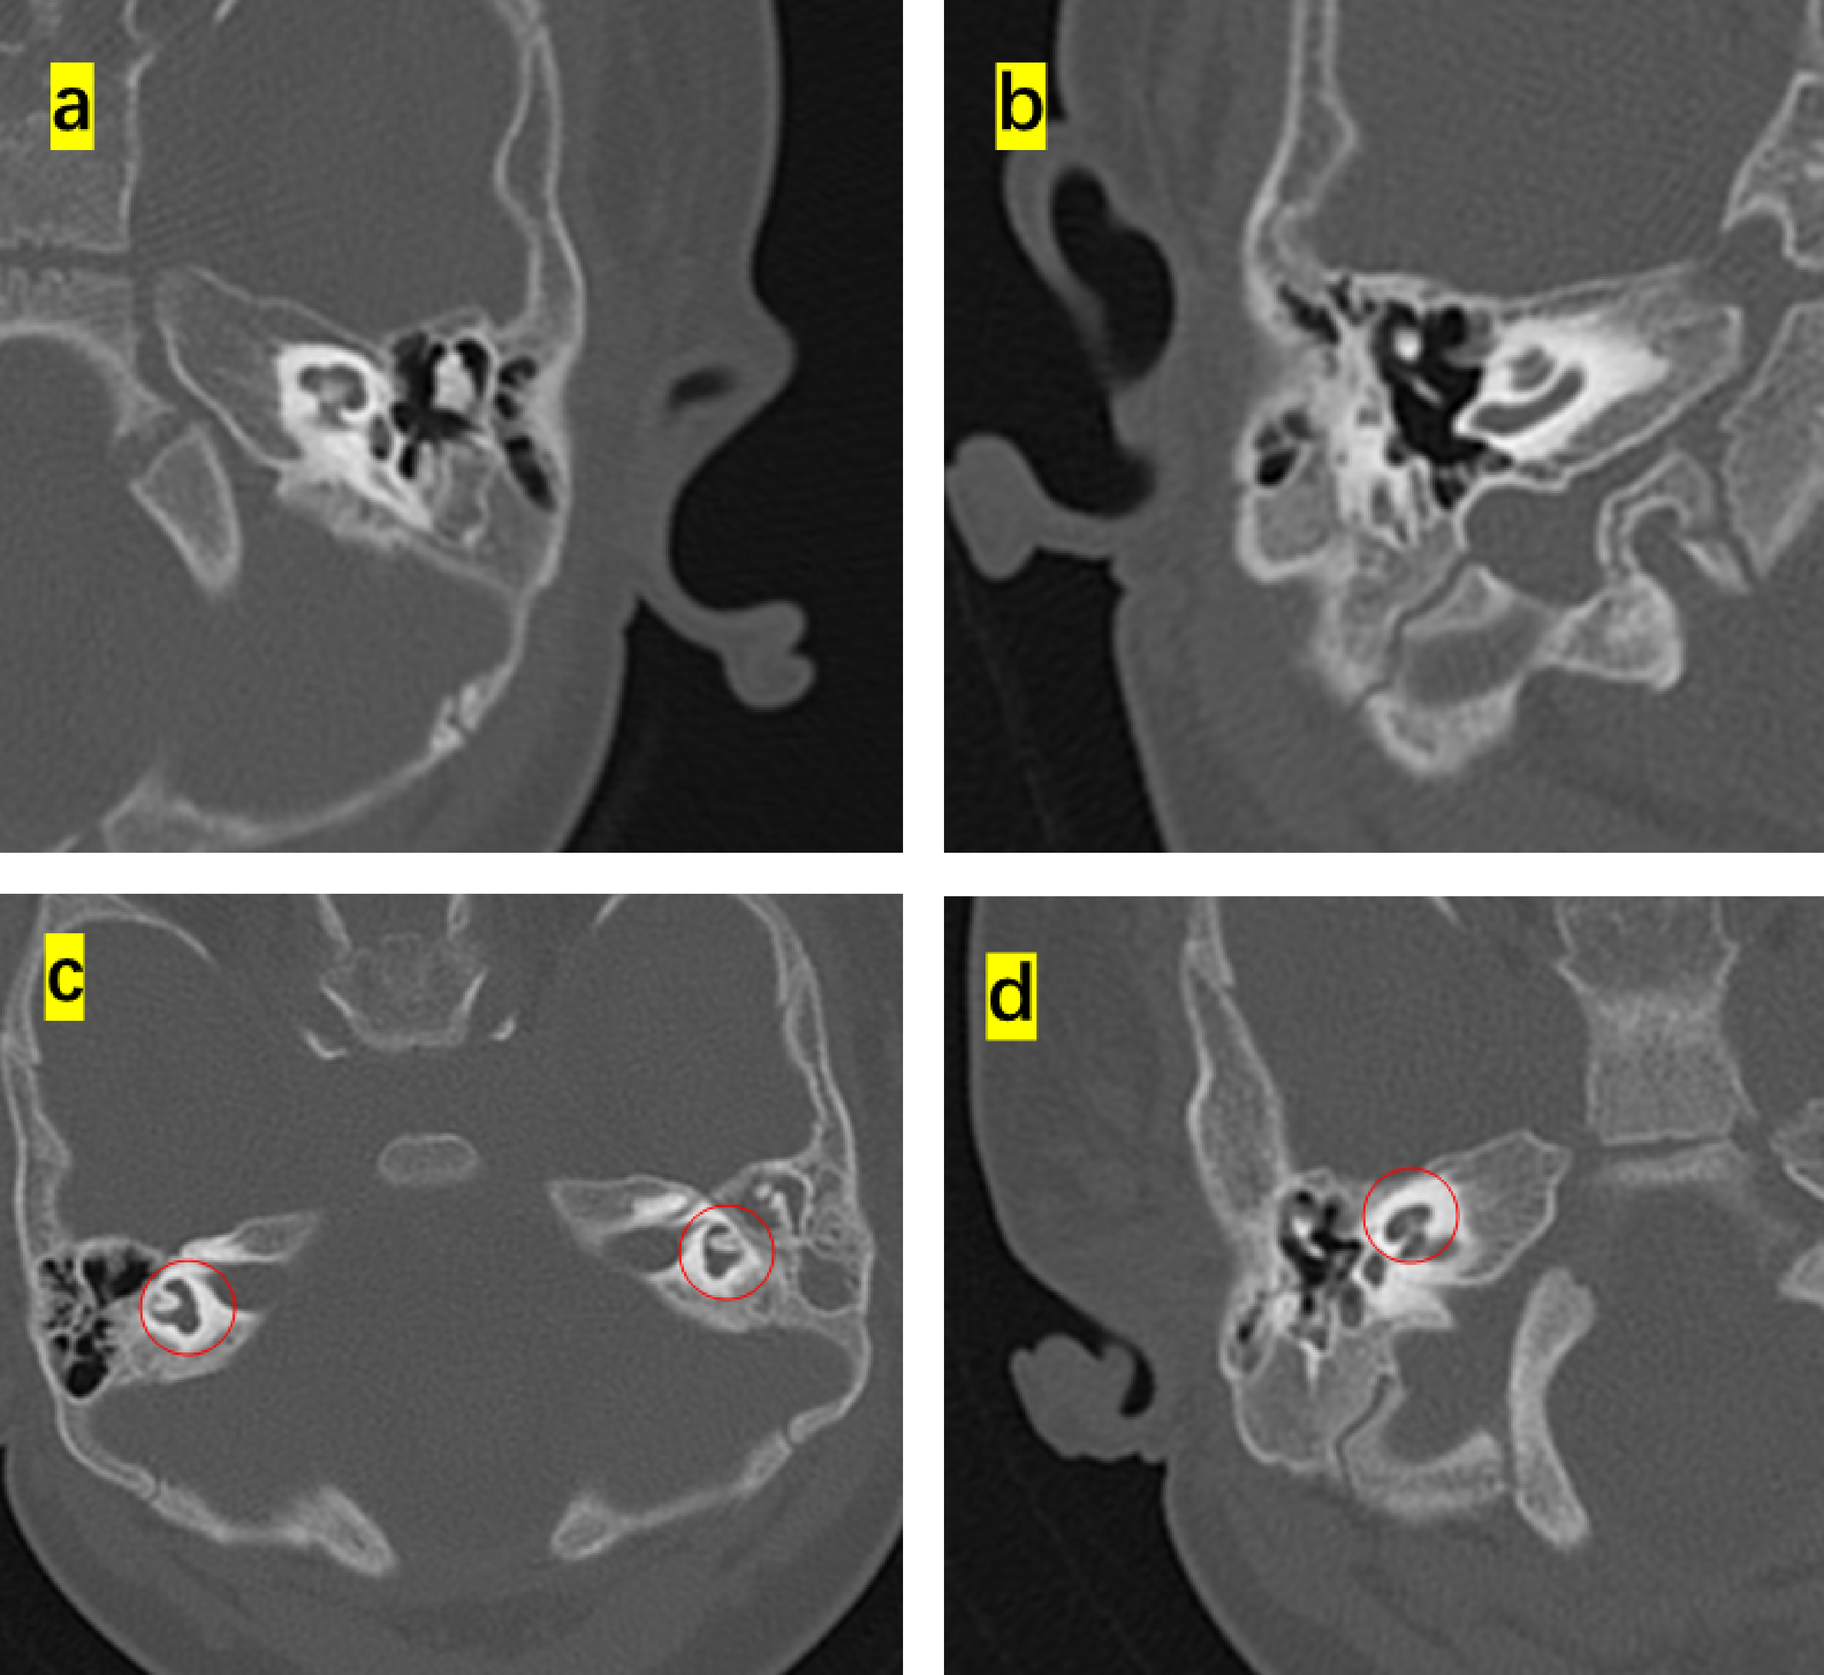

Fig. 1

Ear Computed tomography(CT)scans in Waardenburg syndrome(WS)cases. (a, b) No obvious abnormalities in the middle ear. (c) Vestibular semicircular canal malformation. (d) cochlear apex–middle turn fusion, no obvious cochlear aperture narrowing.